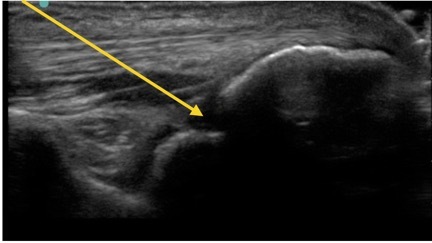

Elbow Posterior Recess Needle Insertion Image

Arrow: Needle Path